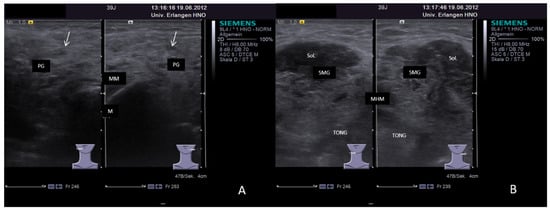

3.2. Findings in Normal Anatomy in Major Salivary Glands

3.4.2. Chronic Recurrent Juvenile Parotitis

3.4.3. Sjoegren’s Syndrome/Disease